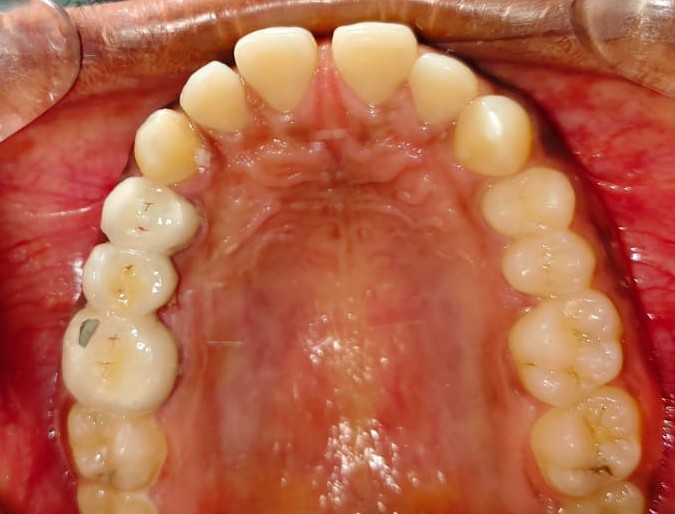

After/Before

See stunning smile transformation before and after